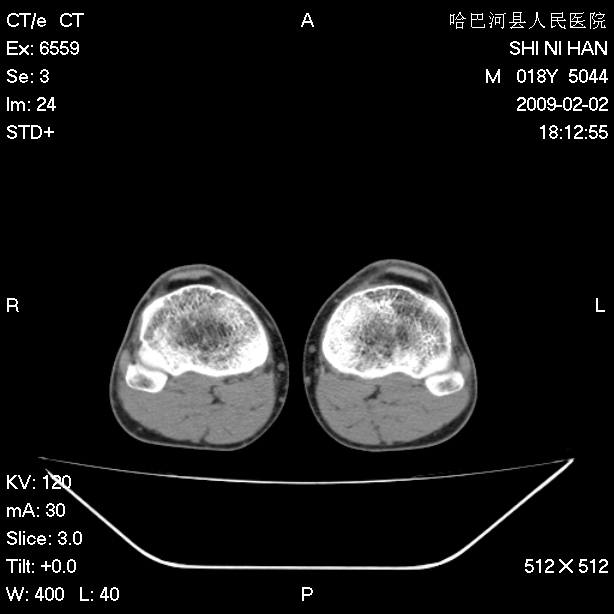

标题: CT17889:外伤后右膝关节反复疼痛3年余 [打印本页]

标题: CT17889:外伤后右膝关节反复疼痛3年余

ct未见明显异常。关节腔未见明显积液,半月板未见明显撕裂。但最好还是mri看看韧带及半月板情况。